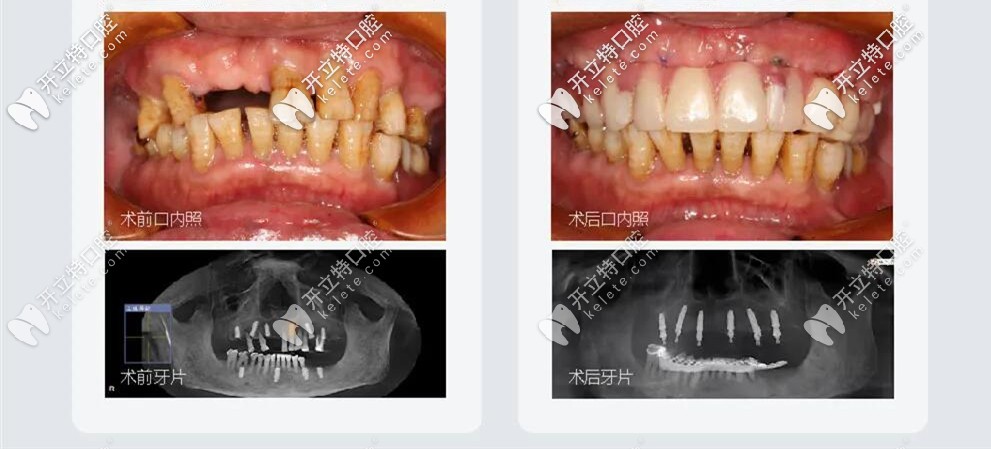

王叔叔已經(jīng)60多歲了,但是口內(nèi)牙齒松動,部分牙齒已經(jīng)缺失,牙齒縫隙大,牙槽骨萎縮,每天吃東西都比較困難;

All-on-6種植牙前后照

王叔叔的孩子們?yōu)榱俗约旱睦习帜馨蚕硗砟?,吃好喝好,在百般勸說下帶著王叔叔來到了成都極光口腔找劉東偉醫(yī)生做的種植牙;劉醫(yī)生結(jié)合顧客需求以及自己的經(jīng)驗,采取的方案是:拔除松動的牙齒,用極光美式定制植牙All-on-6微創(chuàng)種植牙技術(shù);王叔叔當天植牙,當天戴牙;

微創(chuàng)種植牙治療前后對比圖

當天做完種植牙,就恢復咀嚼功能啦,種完就回家了,不腫不痛也很輕松。